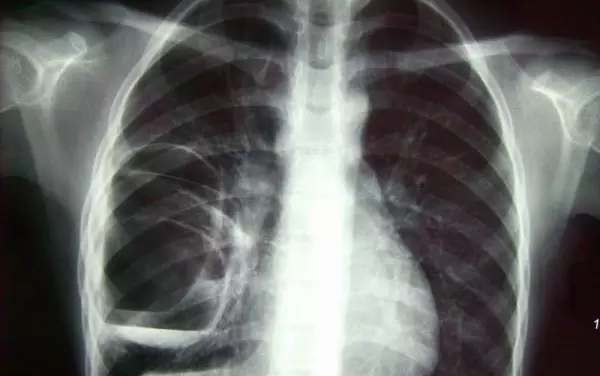

X光攝影(平片)

X光會(huì)穿透人體,由于人體各部位組織密度厚度不同,吸收的X光機(jī)的劑量不同,到達(dá)底片的X光的量不同,底片就會(huì)顯現(xiàn)出黑白不同的顏色。

優(yōu)點(diǎn):快捷、價(jià)廉、影像清晰度高

缺點(diǎn):平片檢查,無法進(jìn)行三維檢查

3、胸部——粗看X光平片,細(xì)看CT

X光胸片可粗略檢查肺、心影、主動(dòng)脈弓、肋骨等,可以檢查有無肺紋理增多、肺內(nèi)較大腫塊、主動(dòng)脈結(jié)鈣化等。胸部CT檢查顯示出的結(jié)構(gòu)更清晰,對(duì)胸部病變檢出敏感性和準(zhǔn)確性均優(yōu)于常規(guī)X光胸片,特別是對(duì)于篩查早期肺癌有重大意義。而磁共振成像對(duì)于肺內(nèi)疾病的診斷,應(yīng)用非常有限。